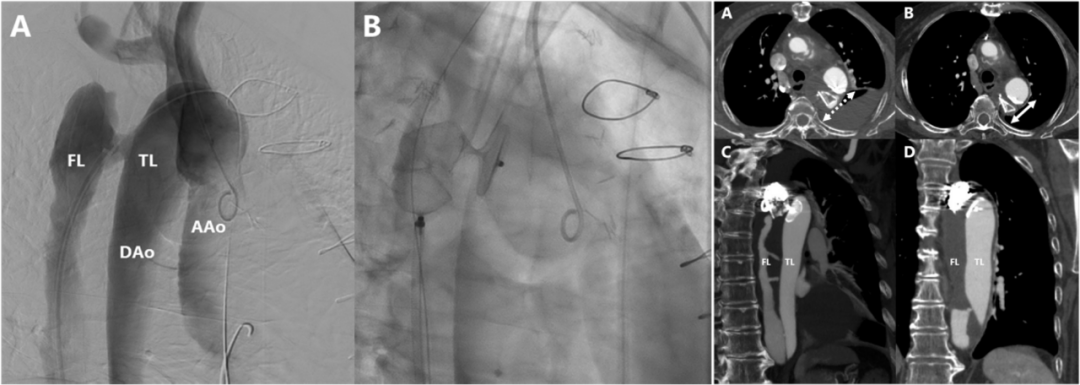

多项研究表明,当通过血管内入路治疗解剖上具有挑战性的主髂动脉瘤疾病时,髂内动脉的栓塞往往是必要且安全的。栓塞髂内动脉不仅是一种安全有效的治疗方法,还增加了腔内修复主髂动脉瘤的适用性。2014年,一项回顾性研究评估2002~2011年间88例在EVAR术前接受了ⅡA栓塞的患者。ⅡA栓塞技术成功率为95.7%,术后38%出现了臀性跛行,10%勃起功能障碍,但无严重臀部缺血并发症。对比单侧和双侧栓塞、同时和分期栓塞,并无统计学差异。在大多数病例中,ⅡA栓塞术是安全有效的,可以防止显著的Ⅱ型内漏。2016年,一项评估EVAR术前栓塞ⅡA盆腔缺血发生率和相关因素的研究,共纳入25例患者,8例(32%)出现新发缺血,包括勃起功能障碍(4%)和臀部跛行(28%),仅4例(16%)持续6个月。进一步分析显示双侧ⅡA栓塞和较短的EVAR时间间隔与风险增加相关(P=0.006和P=0.044)。由此表明,ⅡA栓塞是一种有益的手术,为了最小化臀部跛行的风险,建议不要双侧ⅡA栓塞,适当延长与随后EVAR的时间间隔。2020年,一项纳入了139例主髂动脉瘤患者的回顾性研究,结果表明在EVAR行ⅡA栓塞是安全有效的,大多数患者为未发生(60.0%)或轻度(36.7%)臀部跛行。同年,一项对比ⅡA保留和栓塞疗效的回顾性研究,结果表明ⅡA栓塞技术成功率为100%,ⅡA栓塞常见并发症为臀肌跛行,仅1例ED,无其他严重并发症。4、AVP栓塞ⅡA是一种安全便捷且高效的方法,优于弹簧圈AVP作为栓塞装置,可以促进血液凝固,并对血流形成一道物理屏障,激活机体的免疫系统反应,从而启动机体的自身凝血过程。相较于弹簧圈,AVP是一种可以在高流量血管进行锚定的栓塞材料,更加均匀且致密。

2016年,一项多中心研究分析了2007~2013年间169例接受AVP治疗的临床疗效;研究结果,技术成功率为97.6%,手术平均时长14 min,平均需要1.43个AVP实现栓塞。随访期间未观察到ⅡA再通,证明了AVP的安全性。另外,一项弹簧圈和AVP的对比研究提示,AVP的手术和放射暴露时间更短(59 min vs. 97 min),使用数量更少(1.14 vs. 7.54),治疗成本更低。

另一项对比AVP和弹簧圈栓塞术后并发症的研究,结果显示总的并发症风险较低,常见的是臀部跛行(9.4%)、腹股沟血肿(1.1%)、内漏(5.3%)和勃起功能障碍(1.0%)。而无论是单侧,还是双侧ⅡA栓塞,AVP组臀肌跛行和勃起功能障碍的发生率都低于弹簧圈组。这可能是由于AVP定位准确,不会发生移位,集中于髂内主干,而弹簧圈可能会发生移位,导致栓塞髂内动脉壁支或脏支。此外,AVP成像伪影少,更容易识别可能发生的内漏,不影响EVAR术后影像监测的判断。